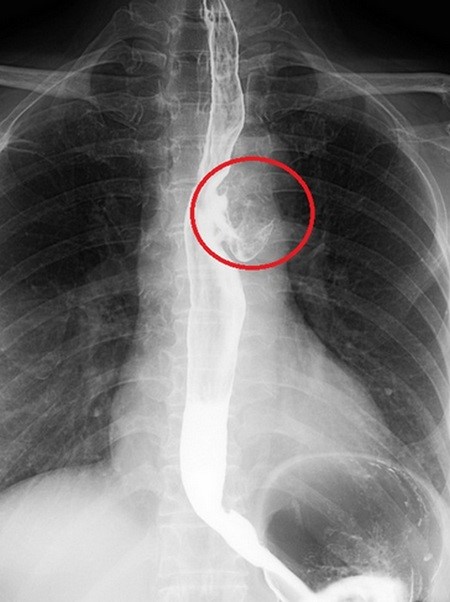

61歲的許女士兩年來一直覺得吃完東西後口腔有明顯異味,就算調整刷牙頻率、更換牙膏以及漱口水都沒有改善,嚴重影響社交生活。經過親友建議,許女士接受胃鏡檢查,結果發現食道異常,透過進一步食道攝影及電腦斷層檢查發現,許女士食道中段有一個3.5公分大的憩室,導致食物殘渣掉入後受細菌分解發酵進而產生異味,經胸腔外科醫師執行胸腔鏡食道憩室手術,將膨出的憩室切除,順利解除許女士的困擾,術後隔日進食也不再受異味影響。

食道憩室一般透過胃鏡檢查進行初步確認,如有結構異常的狀況,則會進一步安排食道攝影及電腦斷層,找出準確位置及憩室大小。

以中、下段食道憩室為例,傳統治療方式需要執行開胸手術,在側胸壁劃出約15公分的傷口,撐開肋骨後進入肋膜腔將憩室切除,而現今胸腔鏡手術則是在肋間透過約2至3公分大的孔洞抵達病灶,並在胸腔鏡及胃鏡的輔助下完成憩室的定位及切除。

目前胸腔鏡手術不僅傷口小、病人疼痛度較低,且預後程度良好,復發率趨近於零,但過程充分考驗醫師經驗,切除過多可能使食道狹窄,切除過少則可能讓憩室再生。現今胸腔鏡技術成熟,能對更複雜的食道癌或縱膈腔腫瘤及淋巴結做精準切除,考量胸腔左側有升、降主動脈等重要血管及神經,所以即使憩室出現在食道左側,醫師通常也可以選擇從右側肋膜腔進入執行手術。